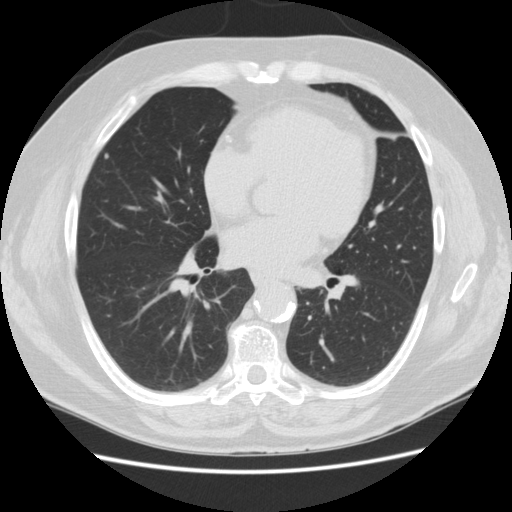

胸部のCT 第4版 | 村田喜代史, 上甲 剛, 村山貞之, 酒井文和 |本。胸部のCT 第4版 | 村田喜代史, 上甲 剛, 村山貞之, 酒井文和 |本。CC3 胸部CTの読影 - YouTube。kokuu 雑穀米 ホワイトブレンド グルテンフリー 2袋。CANON社製新型CT装置を導入 | 新柴又駅前クリニック(脳神経外科)。腹部CTを読影する上で重要な脂肪ウインドウとは? - YouTube。胸部CTの読影の基礎【働くのに必要な知識を最短で習得する方法。胸部CT画像の読影を支援するEIRL Chest CTの販売を開始 - エル。見逃しを防ぐための腹部CTの読影の順番|ごろ〜にゃ@放射線科医。18203920 | 腹部CT CBT | M3E Medical。体幹部領域-Aquilion PRIMEの各領域における技術 - 東芝。CT¹⁾検査|検査ガイド|患者さん向けガイド|原三信病院。腹部CT検査 胆石 - 医療のイラスト・写真・動画、素材販売サイト。胸部と腹部のCTに関する専門書、最新の知見を網羅。- 書籍名: 胸部のCT 第4版- 書籍名: 腹部のCT 第3版- 出版社: MEDSi- 書籍の状態: 良好- ISBN: 9784895921877- ISBN: 9784895921860ご覧いただきありがとうございます。○バラ売り希望にも対応します。(価格は応相談)コメントください!○未使用ですが、自宅保存のため運搬による傷が少しあります。○未使用のためメモなどはありません。カバーも目立った傷はありません。○できるだけ早く発送します。お急ぎの方はコメントください。